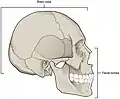

The eight cranial bones. (Facial bones are shown in transparent.)

Yellow: Frontal bone (1)

Blue: Parietal bone (2)

Purple: Sphenoid bone (1)

Brown: Temporal bone (2)

Green: Occipital bone (1)

Red: Ethmoid bone (1) | |

Neurocranium (labeled as "Brain case") and facial bones.

Neurocranium (labeled as "Brain case") and facial bones. -